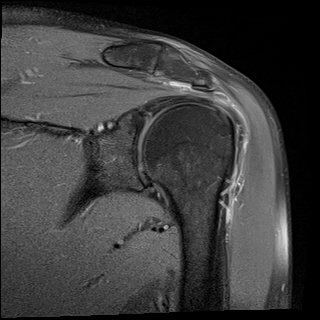

ÀÚ±â°ø¸í°Ë»ç

±Ø»ó°Ç ÆÄ¿­, Á¡¾×³¶¿°, °ßºÀÇÏ °ñ±Ø

¹æ»ç¼±»çÁøÀ̳ª ÀÚ±â°ø¸í°Ë»ç¿¡¼­ °ñ±ØÀÌ °üÂûµÇ°í ±Ø»ó°Ç ÆÄ¿­ÀÌ ÀÖ´Â °æ¿ì °Ë»ç¿¡¼­ º¸ÀÌ´Â

°ñ±ØÀÌ ±Ø»ç°ÇÆÄ¿­ÀÇ ¿øÀÎÀ̶ó°í ÃßÁ¤ÇÒ ¼öµµ ÀÖ´Ù.  ±×·¯³ª ±Ø»ó°ÇÆÄ¿­ÀÌ Ç¥Ãþº¸´Ù´Â ½ÉÃþ¿¡¼­

´õ ¸¹ÀÌ ¹ß»ýÇϰí Áõ»óÀ» ÀÏÀ¸Å°Áö ¾Ê´Â °ñ±ØÀÌ ¸¹Àº Á¡À» °í·ÁÇÒ ¶§ °Ë»ç¿¡¼­ º¸ÀÌ´Â °ñ±ØÀ»

Ä¡·á(°ßºÀ¼ºÇü¼ú)ÀÇ ´ë»óÀ¸·Î ÇÏ´Â °ÍÀº Çϸ®ÀûÀÎ °áÁ¤ÀÌ ¾Æ´Ï´Ù. ÀÌ È¯ÀÚÀÇ °æ¿ìó·³ ±Ø»ó°Ç

³»ÃøÀÇ ºÎÁ¾°ú Ç¥Ãþ ¶Ç´Â ÀüÃþ ÆÄ¿­ÀÌ ÀÖÀ¸¸é¼­ Á¡¾×³¶ÀÇ ºÎÁ¾°ú Ãæµ¹°Ë»ç ½Ã Ãæµ¹ ¼Ò°ßÀ» º¸ÀÌ´Â °æ¿ì¿¡

¹æ»ç¼±À̳ª ÀÚ±â°ø¸í°Ë»ç¿¡¼­ º¸ÀÌ´Â °ñ±ØÀÌ ±Ø»ó°Ç ÆÄ¿­ÀÇ ¿øÀÎÀ¸·Î ÃßÁ¤ÇÒ ¼ö ÀÖ´Ù.